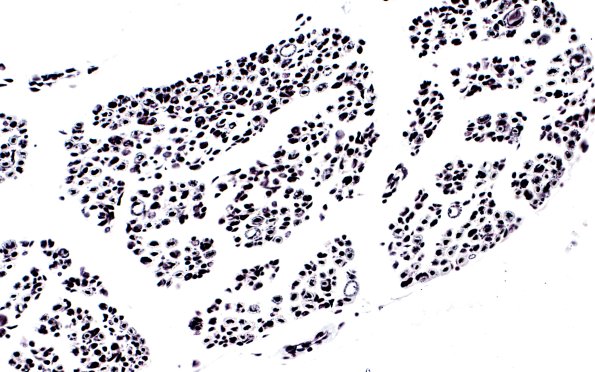

Washington University Experience | PERIPHERAL NEUROPATHY | 7A GUILLAIN-BARRE SYNDROME (GBS) | 9A4 GBS (Case 9) Bodian 40X 1

Cross sections of spinal roots stained for myelin (LFB-PAS, 9A3) and axons (Bodian, 9A4) show myelin loss with relative preservation of axons.